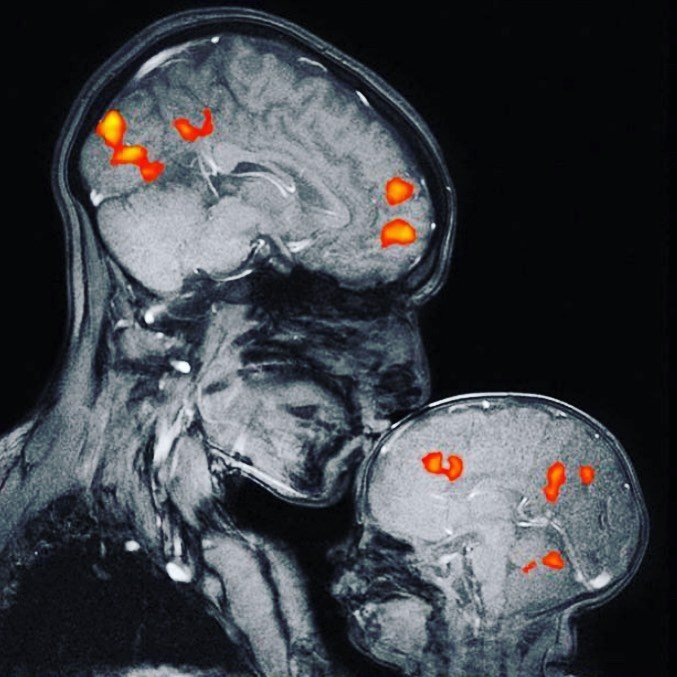

Впервые получено фото мозга во время поцелуя. На фото, полученном с помощью МРТ, нейробиолог Ребекка Сакс из Массачусетского технологического института и ее двухмесячный сын во время поцелуя. Видите, как сразу несколько зон просыпаются и начинают «светиться», как бабочки ))

Это первое в мире изображение МРТ, показывающее связь матери и ребенка. На снимке невролог Ребекка Сакс целует своего двухмесячного сына.